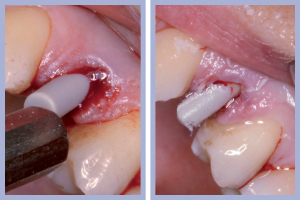

- Figg. 4a, b – Scollamento

- Figg. 5a, b – Estrazione dei canini da latte

- Figg. 6a, b – Estrazione dei canini da latte

- Figg. 7a, b – Toilette chirurgica

- Figg. 8a, b – Mappatura alveolare tramite sonda parodontale